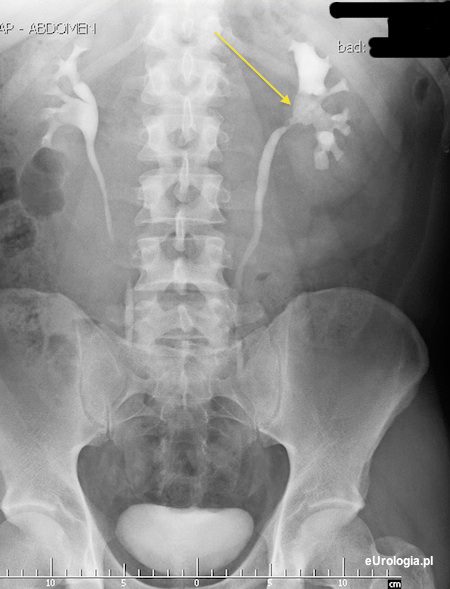

Fot. Ubytek wypełnienia w miedniczce nerkowej - obraz kamicy odlewowej miedniczki po stronie lewej.